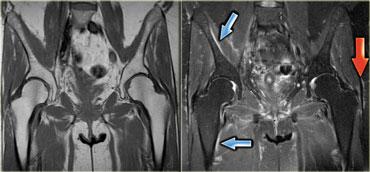

Hình bên trái là một bệnh nhân viêm đa cơ (PM), một trong các thể bệnh cơ viêm.

Các cơ lớn ở gốc chi bị tổn thương, thường theo hình thái đối xứng.

Nhìn chung, không phải tất cả các cơ đều bị tổn thương, do đó MRI có thể giúp xác định vị trí tốt nhất để sinh thiết.

Đôi khi MRI toàn thân được sử dụng để chẩn đoán và theo dõi viêm đa cơ sau khi đã bắt đầu điều trị bằng corticosteroid.

Hình bên trái là một bệnh nhân viêm cơ thể vùi.

Lưu ý tổn thương đối xứng của cơ tứ đầu đùi và sự vắng mặt của phù nề ở các tổ chức xung quanh.